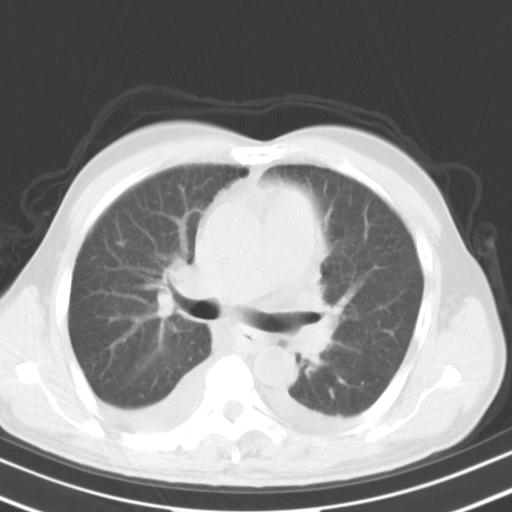

以下是引用zjzjr在2010-3-21 17:39:00的发言:[br]右下中心型肺癌并阻塞性肺炎/不张,纵膈淋巴结肿大,右侧大量胸腔积液,左侧少量胸腔积液

以下是引用zxl51642在2010-3-21 17:06:00的发言:[br]右下中心型肺癌并阻塞性肺炎/不张,纵膈淋巴结肿大,右侧大量胸腔积液,左侧少量胸腔积液,少量腹水。建议纤维支气管镜进一步检查。